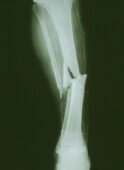

(美联社电)一项新研究发现,肾结石患者的骨头相对常人更易受伤,在治疗肾结石的同时,也应增加对于患者骨质情况的监控和治疗。

麦克医生和他的团队对这些人进行了长达5年的案例跟踪,结果发现肾结石患者骨折的概率极高,且这种骨质方面的伤害遍及全身。

其中,男性肾结石患者相较常人骨折概率高出10%,而在青少年时期的男性病例中,这样的概率高出竟55%!

针对20至60岁的女性患者,她们较常人骨折的概率会高出17%到52%,此情况对30-39的女性患者尤甚(美国肾脏病学会临床杂志称)。

虽然此项研究仅能证明肾结石与骨折之间有所联系,而不是绝对性的绑定联系,但是足以使我们对肾结石患者的骨骼问题引起重视。